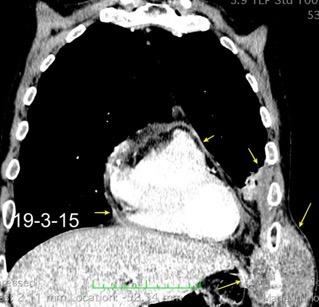

Marzo 2014: Perforación longitudinal distal secundaria a episodio de vómito (síndrome de Boerhaave). Derrame pleural izdo. que evoluciona a empiema.

Wang C-T et al. Tension hydropneumothorax in a Boerhaave syndrome patient: A case report . World J Emerg Med, 2021. Katabathina V et al. Nonvascular, nontraumatic mediastinal emergencies in adults:a comprehensive review of imaging findings. Radiographics. 2011.